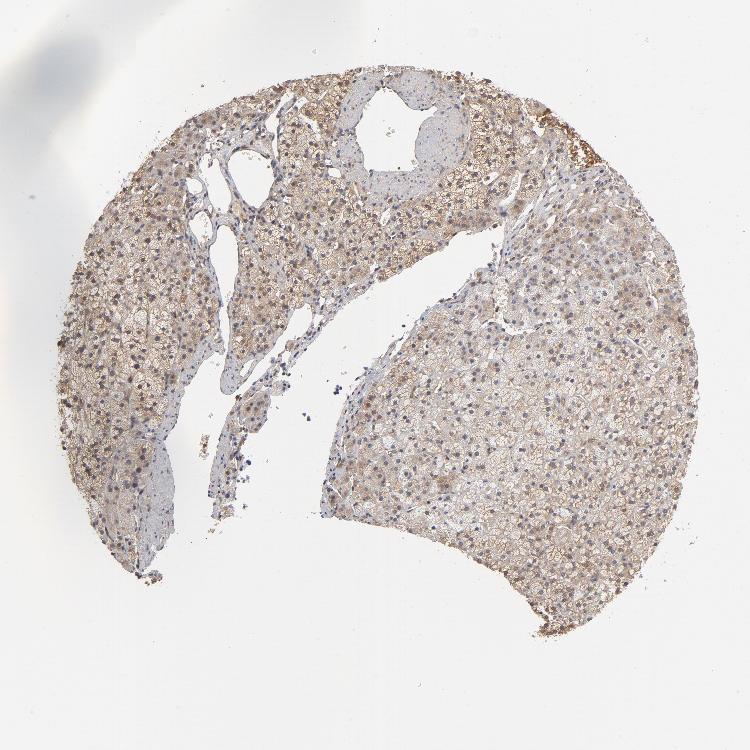

ADRENAL GLAND - Antibody stainingi

Antibody staining in the annotated cell types in the current human tissue is reported as not detected, low, medium, or high, based on conventional immunohistochemistry profiling in selected tissues. This score is based on the combination of the staining intensity and fraction of stained cells.

Each image is clickable and will lead to virtual microscopy that enables deeper exploration of all samples and also displays staining intensity scores, fraction scores and subcellular localization as well as patient and tissue information for each sample.

Antibody HPA003630Antibody HPA021865

Glandular cells LowHigh